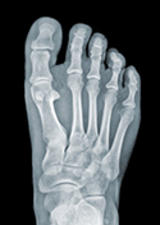

Foot pain (navicular stress fracture study)

The Bone Lab is recruiting participants between the ages of 18-50 that are experiencing foot pain or tenderness that may suspect a navicular stress fracture. These stress fractures are common among individuals that take part in jumping or running type activities. If you are interested in taking part in this study or learning more, please contact bonelab@ucalgary.ca